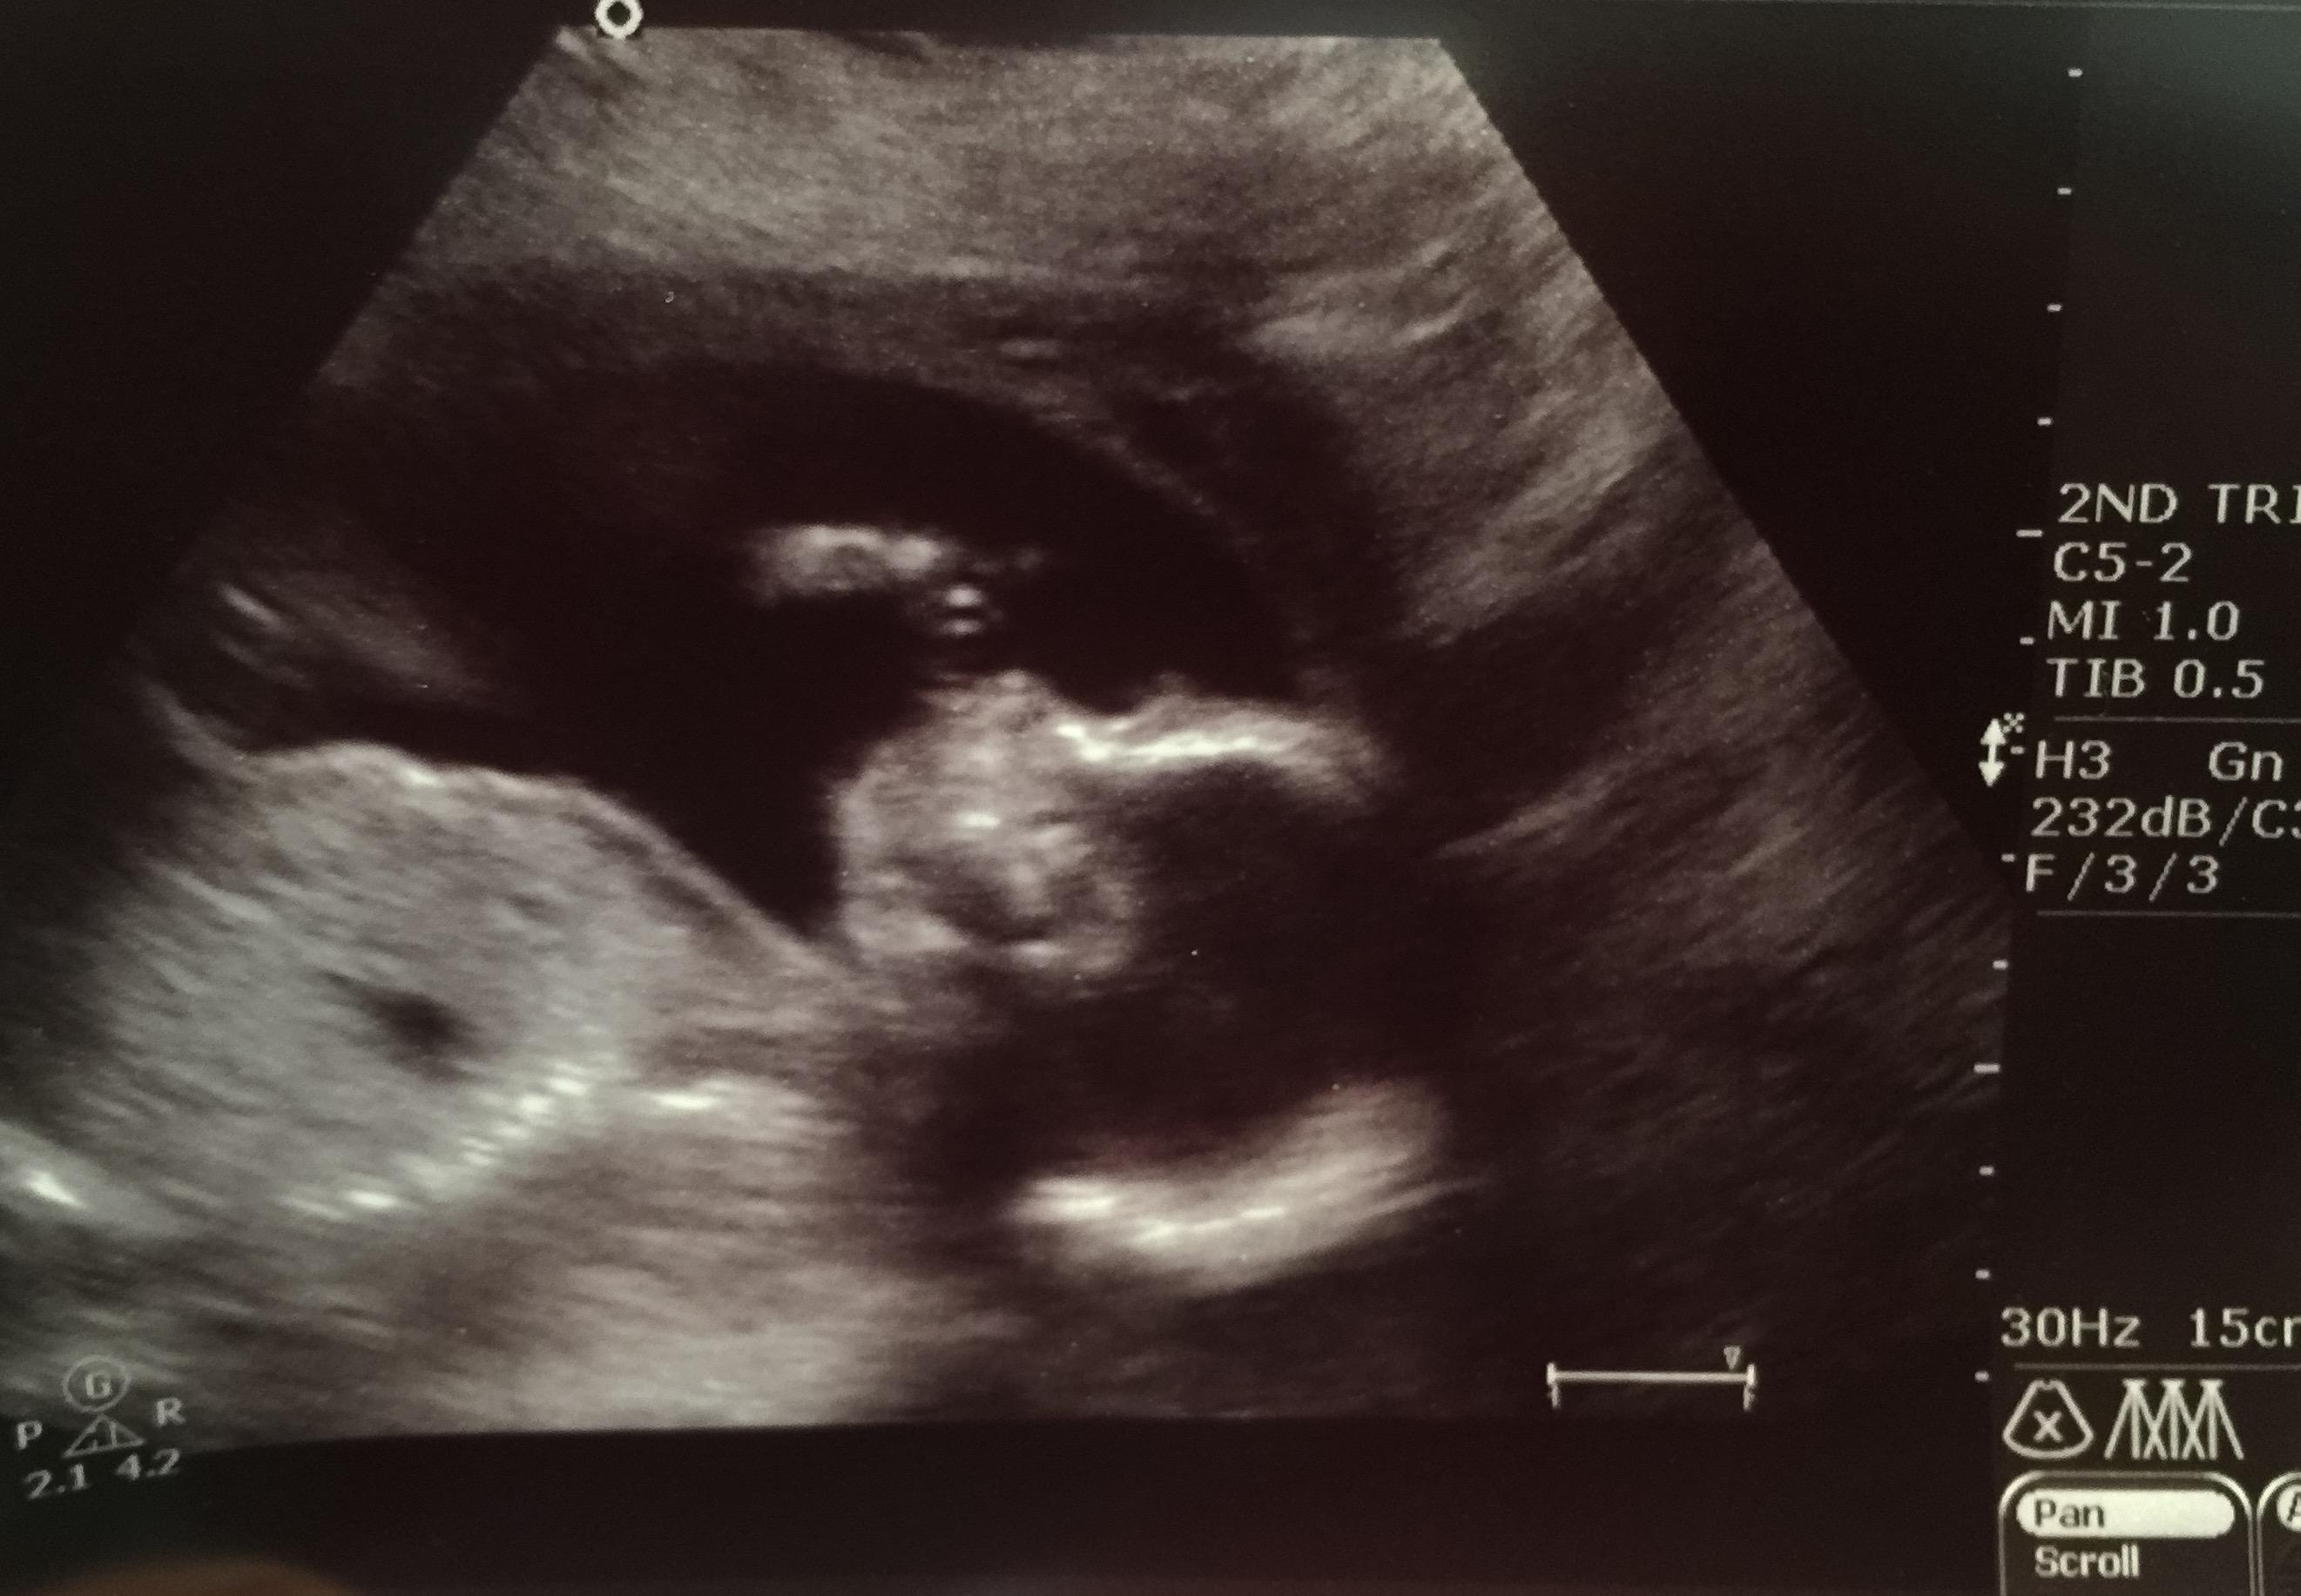

20 weeks today and we were SO excited for our big ultrasound. We went in and had a beautiful scan, lots of baby girl holding her toes, sucking her thumb and kicking me like crazy. Then...we waited and waited for the doctor to come back and see us. Our hearts sunk when she started telling us about the extra fluid that surrounded both of her kidneys but we were then somewhat reassured when the doctor said that this can be normal and can resolve on its own. For a second we breathed a sigh of relief until she followed with "but, there was something else." The doctor told us that our little one has bilateral (both sides) choroid plexus cysts in her brain. She told us not to get too worried yet, that these too can be normal but since I have another "marker" with the fluid surrounding her kidneys, she recommended that we see a specialist to have a more in depth ultrasound and more specific labs done since we had opted out of the quad screening earlier in the pregnancy.

(edited to add pictures- sorry I couldn't figure out how to make them smaller)